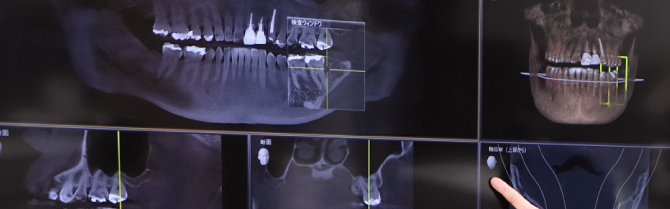

診査・診断・治療計画

診査・診断・治療計画は、オールオン4を成功に導くために必要なとても大事なステップです。

3Dスマイルデザイン、ワックスアップ、ラジオグラフィックガイド等によるプランニングに基づいて、患者様それぞれに合わせたオーダーメイドの治療を慎重に進めていきます。